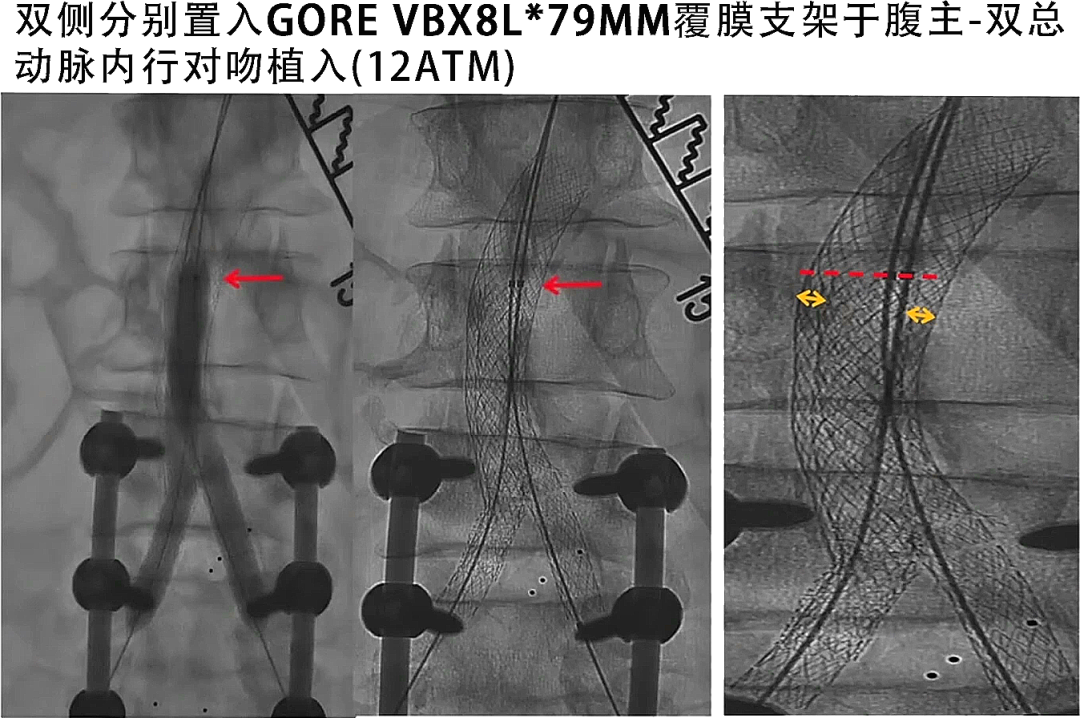

主要器械:GORE VBX 8L*79mm球囊扩张覆膜支架*2

VBX支架定位:

a) 远端需完全覆盖原右侧裸支架,且保留髂内动脉

b) 近心端确保在腹主动脉腔内平齐

c) 双侧同时球囊扩张,最大扩张压力12atm,确保双侧球扩覆膜支架在腹主动脉段呈“Double-D”形状完全打开,最大程度减少覆膜支架与腹主动脉壁间的空隙

寇镭主任手术后总结戈尔VBX的使用经验,在本例手术中使用的8mmVBX其直径可后扩到8mm-16mm,没有明显短缩。利用其可变径的产品特性和对吻操作技术可使其在腹主动脉支架内呈DOUBLE-D形态打开,最大程度减少假腔,其远期通畅率值得期待。